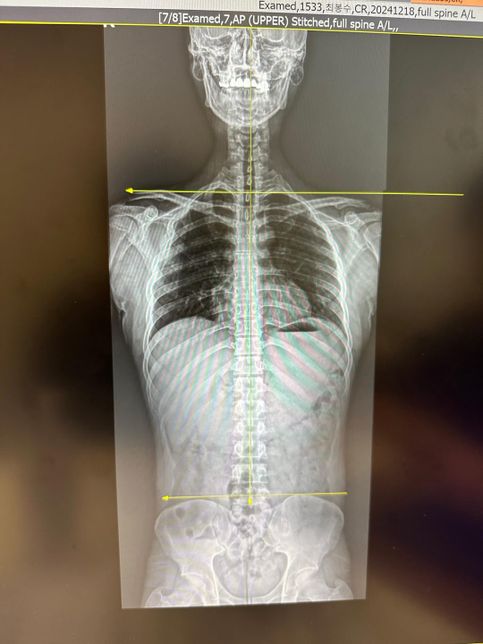

- 정형외과의료상담Q. 한쪽 어깨 찝힘이 발생해서 엑스레이를 찍어봤습니다..엑스레이 사진상에 보시면 제 기준 오른쪽(사진 기준 왼쪽) 어깨가 찝히는 상황이 자주 발생합니다.특히 운동을 할때 오른쪽 어깨쪽이 짧아져 있고, 미는 운동을 할때에도 오른쪽만 불편감을 호소하게 됩니다.그래서 엑스레이를 찍어보니 사진과 같이 양쪽 어깨 길이가 다르고, 어깨관절이 견봉쪽에 촥 달라붙어있어서 찝히는 느낌이 드는게 아닌가 합니다..평소에도 오른쪽 가슴근육만 짧아졌다고 느껴져서 스트레칭을 따로 해주고 있습니다.어깨관절을 다시 원상태로 되돌려 놓으려면 어떻게 해야 하나요..?가슴근육과 견갑하근쪽을 풀어주면 좋아질까요..?이미지가 포함된 질문이에요.

- 재활·물리치료의료상담Q. 한쪽어깨 찝힘이 발생해서 엑스레이를 찍어봤습니다..엑스레이 사진상에 보시면 제 기준 오른쪽(사진 기준 왼쪽) 어깨가 찝히는 상황이 자주 발생합니다.특히 운동을 할때 오른쪽 어깨쪽이 짧아져 있고, 미는 운동을 할때에도 오른쪽만 불편감을 호소하게 됩니다.그래서 엑스레이를 찍어보니 사진과 같이 양쪽 어깨 길이가 다르고, 어깨관절이 견봉쪽에 촥 달라붙어있어서 찝히는 느낌이 드는게 아닌가 합니다..평소에도 오른쪽 가슴근육만 짧아졌다고 느껴져서 스트레칭을 따로 해주고 있습니다.어깨관절을 다시 원상태로 되돌려 놓으려면 어떻게 해야 하나요..?가슴근육과 견갑하근쪽을 풀어주면 좋아질까요..?이미지가 포함된 질문이에요.